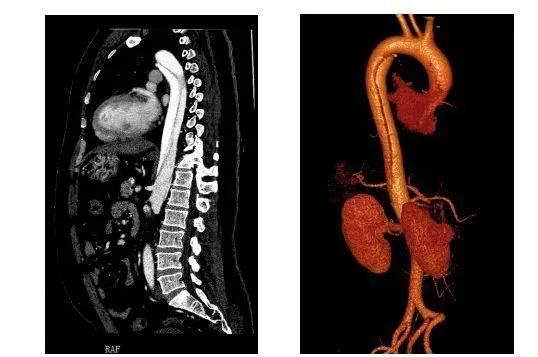

主动脉是人体最粗大的主干血管,直接由心脏发出,承受直接来自心脏泵血强大压力。正常人体动脉血管壁由三层结构组成,由内而外分别是内膜、中层和外膜,三层结构紧密贴合,共同承受血流的压力。主动脉夹层是指主动脉内膜局部出现破口,主动脉腔内的血液从破口进入主动脉壁间隙内,使主动脉壁中层剥离,强有力的血液继续冲击且沿主动脉纵轴扩展,内膜逐步剥离,在动脉内形成真、假两腔,形成夹层,并导致难以忍受的撕裂样疼痛。

确诊主动脉夹层的主要辅助检查手段是:CT血管造影(CTA),磁共振检查(MRA)或是直接的数字剪影血管造影(DSA)。其中CTA检查速度快,是最主要的检查,对于孕妇可以做MRA无放射线辐射,对胎儿也没有影响。